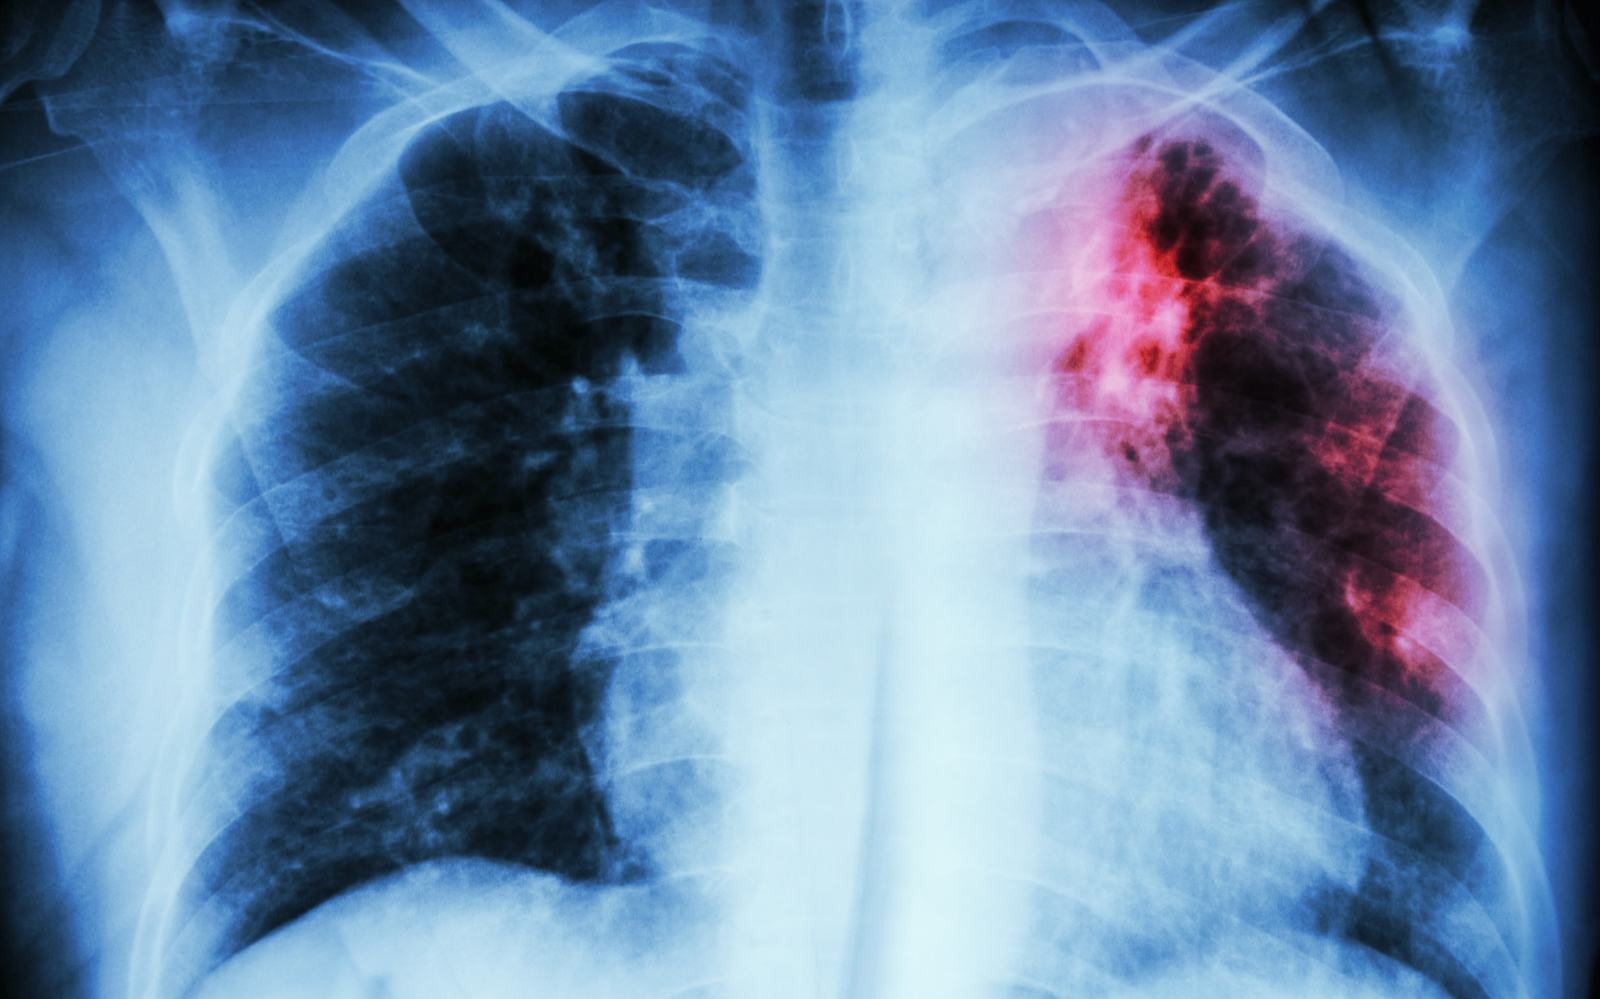

Blood-based TB test will provide a low-cost option for developing nations

The World Health Organization has been calling for the development of a blood-based triage test for active tuberculosis (ATB) — one that's accurate and cheap enough for use in developing nations where most TB-related deaths occur. Sputum-based tests are typically slow and require infrastructure some local communities in developing regions may not have. Now, a team of researchers have developed a blood-based test, which can be configured into a $2 consumable version that delivers results in 30 minutes.